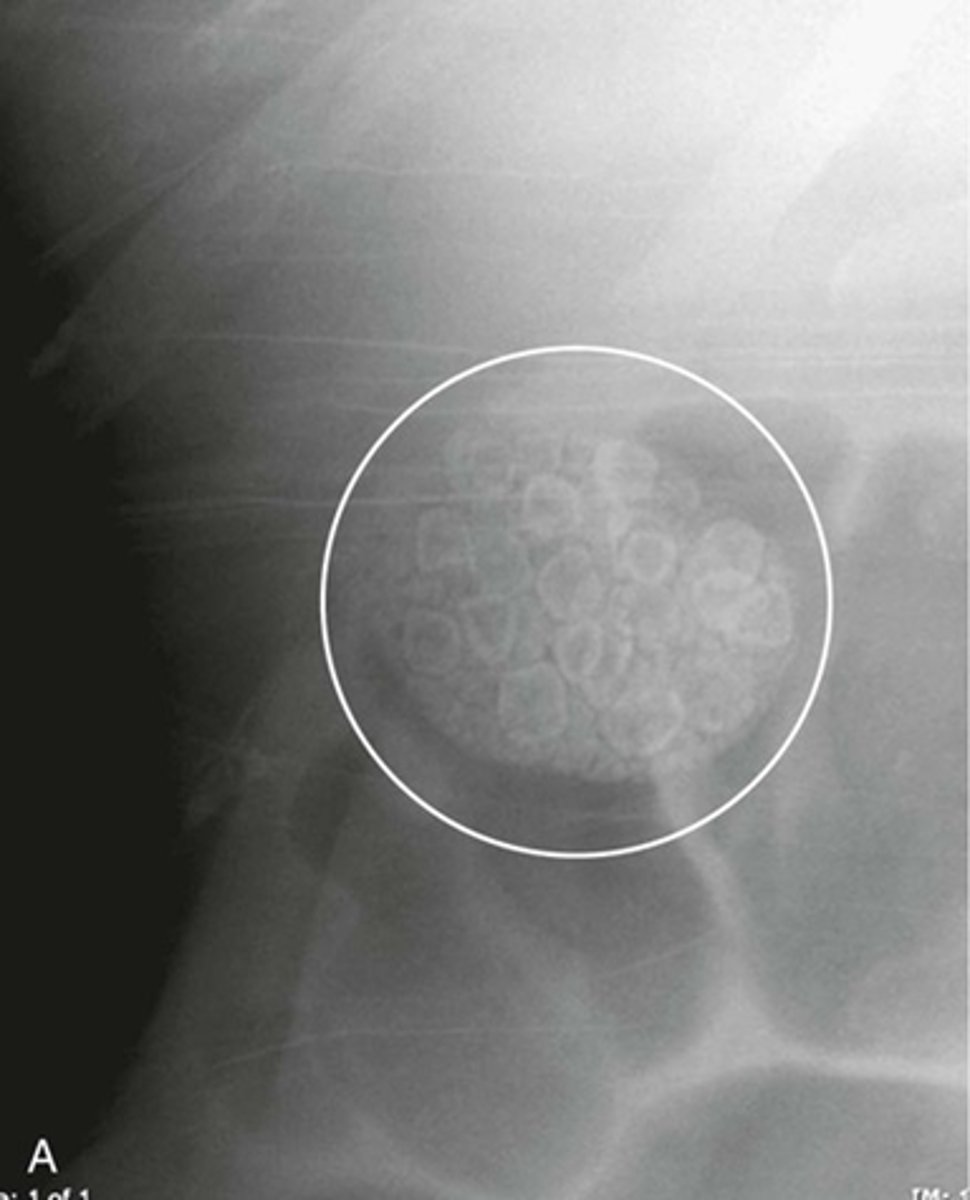

Gallstones

WHITE CIRCLE: multiple lamellar calcification, with interlocking edges that suggest that they all formed in a hollow viscus in proximity to each other.

WHITE ARROW:

gall stones in RUQ, two have central nidus surrounded by laminated concnetric rings of noncalcified and calcified material.

BLACK ARROW:

gall bladder containing bile fats and less dense than adjacent liver.